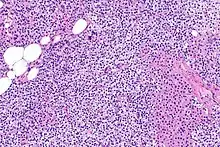

La hiperplasia primaria de la glándula paratiroides se debe tanto a la hipocalcemia como al aumento de los niveles de fosfato al disminuir la expresión de los receptores de vitamina D en la glándula paratiroidea.[8][4] Esta disminución en la expresión de receptores conduce a un hiperfuncionamiento de la paratiroides. Se cree que la hiperfunción de la glándula paratiroidea exacerba la hiperplasia primaria que evoluciona a una hiperplasia secundaria más agresiva. Histológicamente, estas glándulas pueden ser difusas o nodulares.[24] La hiperplasia primaria, que por lo general se trata de un crecimiento policlonal difuso, está relacionada con el hiperparatiroidismo secundario reversible. La hiperplasia secundaria de la glándula paratiroides es más a menudo un crecimiento monoclonal nodular que sostiene el hiperparatiroidismo secundario y es el catalizador en la progresión al hiperparatiroidismo terciario. Las glándulas hiperplásicas nodulares en el hiperparatiroidismo terciario son claramente más grandes tanto en tamaño absoluto como en peso. Se han informado de aumentos de 20 hasta 40 veces.[25][26]

Las glándulas paratiroides están normalmente compuestas de células principales, adipocitos y células oxifílicas esparcidas.[27][14] Se piensa que las células principales son las responsables de la producción, almacenamiento y secreción de hormona paratiroides. Estas células aparecen claras y oscuras con un aparato de Golgi prominente y retículo endoplásmico. En micrografías con microscopio electrónico, las vesículas secretoras se pueden ver dentro y alrededor del aparato de Golgi y en la membrana celular. Estas células también contienen grasa citoplásmica prominente. Al inicio de la hiperplasia, estas células están descritas formando un patrón nodular con aumento de la maquinaria de síntesis de proteínas como el retículo endoplásmico y el aparato de Golgi. También se aumenta el número de vesículas secretoras que puede ser vistas y disminuye la grasa intercelular.[24] Las células oxifílicas también parecen hiperplásicas, sin embargo, estas células son mucho menos prominentes.

Bioquímicamente, hay cambios en la función entre las glándulas paratiroides hiperplásicas normales y nodulares. Estos cambios implican la expresión de protooncogenes y activación de rutas proliferativas, mientras que se inactivan las rutas apoptóticas.[28] En el tejido paratiroideo nodular, el aumento de la expresión de TGF-α, un factor de crecimiento, y EGFR, su receptor, da como resultado una proliferación agresiva y una mayor regulación a la baja de los receptores de vitamina de, que actúan para suprimir las secreciones hormonales.[25][8] Además, se aprecia que el marcador de proliferación Ki67 se expresa en gran medida en el estado hiperplásico nodular secundario. Se ha destacado que los genes supresores de tumores se encuentran silenciados o degradados en el tejido paratiroideo hiperplásico nodular. Uno de estos genes, p53, regula múltiples rutas de supresión de tumores y en la oncogénesis puede ser degradado por b-catenina. Esta ruta está en parte mediada por CACYBP, que se expresa en gran medida en la hiperplasia paratiroidea nodular.